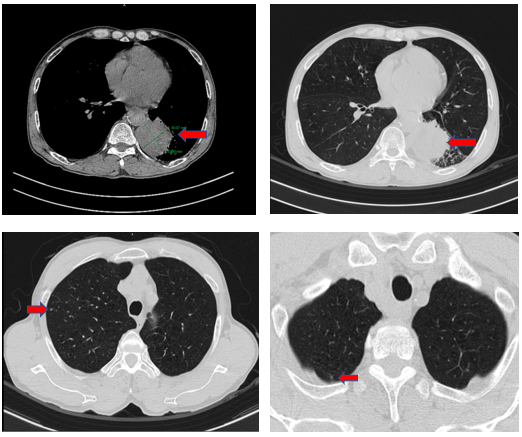

Chụp cắt lớp vi tính lồng ngực: Phổi trái nhu mô thùy dưới S6 có khối tổ chức kích thước 56x50mm, bờ không đều, có cắt cụt nhánh phế quản lân cận, khối tiếp giáp sát màng phổi trung thất. Phổi phải thùy trên có vài nốt đặc nhỏ nằm sát màng phổi đường kính lớn nhất 4mm. Trước carina, cạnh khí quản có hạch lớn nhất kích thước 16x12mm.

Hình 1: Hình ảnh chụp cắt lớp vi tính lồng ngực: hình ảnh khối u kích thước lớn thùy dưới phổi trái và các nốt đặc di căn phổi đối bên